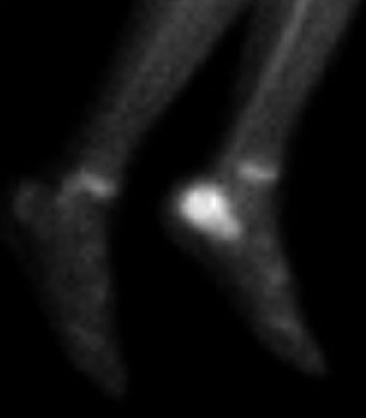

Hay un tiempo de 3 semanas para presentar hallazgos que sugirieran infección en la radiografía simple [5]. Debido a la poca especificidad con la radiografía simple, se recomienda la gammagrafía ósea que puede mostrar resultados desde 24-48 horas después del inicio de la infección [6].

La gammagrafía ósea fue realizada en 3 pacientes, con el 100% de positividad para infección (Figura 4).

El papel de las imágenes es importante como parte del diagnóstico de la enfermedad. Los hallazgos de radiografía son muy inespecíficos y se presentaron en el 50% de los pacientes del estudio y orientaban hacia un proceso infeccioso en el 50% de ellos de forma clara. La resonancia magnética y la gammagrafía aportan información valiosa acerca de procesos infecciosos osteoarticulares. En los 6 pacientes de este estudio en los que se realizó la RM, 5 reportaron cambios compatibles con una infección del calcáneo. La resonancia tiene una sensibilidad y especificidad altas para el diagnóstico de la lesión.